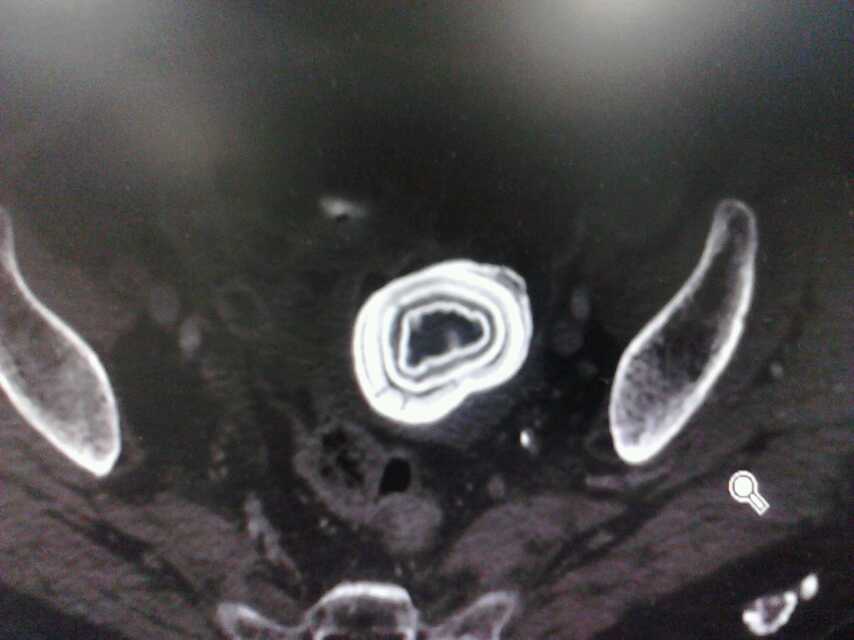

粪石

患者老年女性,腹部CT示肠腔内一巨大粪石,直径约4cm,位于回盲部以上。